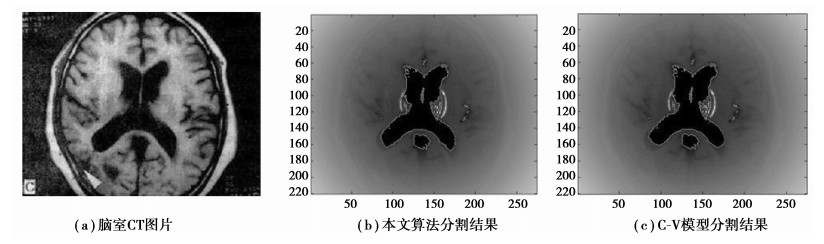

从图中脑室CT图像分割结果(图 4)来看,Chan-Vese模型分割方法在灰度值变化剧烈时能量最小化效果显著,能够准确判断并继续演化,但是在灰度变化缓和时,能量函数对停止收敛的判断存在很大的不确定性,导致最终分割过早结束,产生不完全分割的结果。而笔者提出的方法则大大改善了原方法这一缺陷,在腰部及右下尖锐边缘处很好地跟踪捕捉到了目标边缘,扩大了分割结果的有效面积。另一方面,Chan-Vese模型的最优化结果需要对整张图像素点的遍历,导致算法需要花费大量时间。笔者引入阈值算法预分割,阈值分割初步地排除掉大部分干扰算法分割,缩小算法遍历定义域,在进一步的Chan-Vese模型分割时大大减少了遍历的像素点,再结合尺度变化后保证了水平集的演化速度,最终达到了节省大量分割时间的目的。从图 5中可看出改进C-V算法的有效面积明显增大,图 6反映了改进C-V算法对复杂边缘良好的追踪。

图 4 两种算法对图像分割结果 |